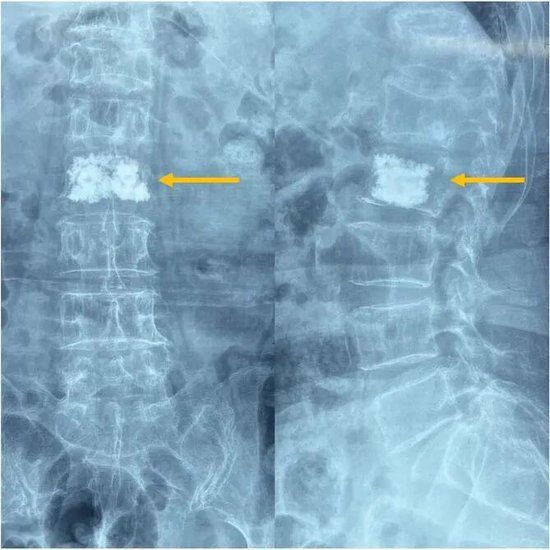

针对椎体压缩骨折:椎体成形术

通过几毫米的细针,向骨折椎体内注入 “骨水泥”,如同为塌陷的椎体注入 “混凝土”,可迅速稳定骨折部位,恢复椎体支撑力。术后患者腰部疼痛立竿见影缓解,第二天就能佩戴腰围稳稳走路。

微创技术不仅有效解决了病痛,还大幅缩短了患者卧床时间,避免了长期卧床可能引发的肺炎、血栓等并发症,助力老年人快速回归正常生活。